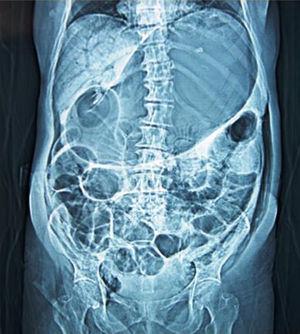

A 56-year-old woman was admitted to the emergency room with a one-day history of abdominal distension and epigastric pain. She started having symptoms after bowel preparation for colonoscopy. Abdominal CT scan showed an extremely distended stomach and small bowel (Figure 1), as well as gas in the hepatic-portal veins (Figure 2). Hepatic portal venous gas is a rare condition that occurs when intraluminal gas enters the portal venous circulation. Although there have been numerous reported causes, the majority are due to intestinal ischemia, with an estimated mortality rate of 75–80%. Mucosal barrier disruption of any kind can theoretically result in hepatic portal venous gas, but it appears to be more common in intestinal ischemia, inflammatory bowel disease, and peptic ulcer disease. Iatrogenic mucosal tears from endoscopy can also result in this situation. Diagnosis is usually made by plain abdominal radiography, sonography, color Doppler flow imaging, or computed tomography scan. An abdominal CT scan showed the classic sign of dilated vessels extending to within 2 cm of the liver capsule, in contrast to biliary gas, which ends up collecting centrally as a result of the centripetal movement of bile.

Figure 1.